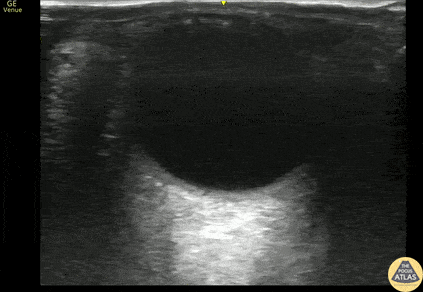

Orbital - Lens Subluxation

Middle aged male with prior bilateral lens replacement presented with atraumatic vision loss. POCUS performed that demonstrates subluxed lens without retinal detachment. Discussed with ophthalmology and pt was discharged with 24 hour follow up with ophthalmology, with eventual plan for operative repair. Michael Maurantonio, PGY3, Denver Health Residency in Emergency Medicine Michael Del Valle, Fellow, Denver Health Ultrasound Fellowship